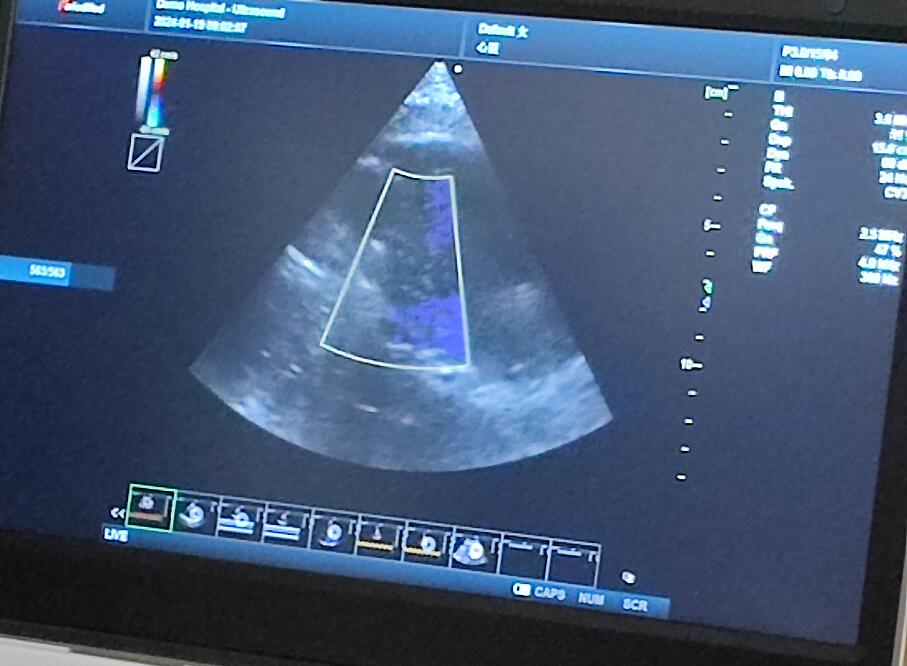

當(dāng)天的超聲培訓(xùn)現(xiàn)場(chǎng)氣氛熱烈非凡,來(lái)自普邁思醫(yī)療事業(yè)部的同仁們紛紛積極參與,滿懷期待地聚集在講臺(tái)周?chē)?,他們的眼神充滿了對(duì)新知識(shí)的渴望和對(duì)技術(shù)提升的執(zhí)著追求。老師身邊里三層外三層圍滿了學(xué)員,大家或是聚精會(huì)神聆聽(tīng)講解,或是踴躍提問(wèn),交流互動(dòng),濃厚的學(xué)習(xí)氛圍讓整個(gè)場(chǎng)地顯得熱鬧非凡,盡管空間狹小,但阻擋不住的是每一位參與者內(nèi)心深處對(duì)于專(zhuān)業(yè)技能提升的決心與毅力。

授課的專(zhuān)家老師被這股澎湃的學(xué)習(xí)熱情深深打動(dòng),她的臉上洋溢著欣慰和鼓舞的笑容。面對(duì)這樣一群如饑似渴的學(xué)子,老師更是傾盡全力,毫無(wú)保留地將自己豐富的臨床經(jīng)驗(yàn)和深厚的專(zhuān)業(yè)理論知識(shí)悉數(shù)傳授,詳細(xì)解答每一個(gè)問(wèn)題,用心指導(dǎo)每一次操作演練。她表示,普邁思醫(yī)療事業(yè)部團(tuán)隊(duì)展現(xiàn)出的這種敬業(yè)精神和積極向上的風(fēng)貌讓她深受感染,還給予了他們高度評(píng)價(jià)和嘉許。